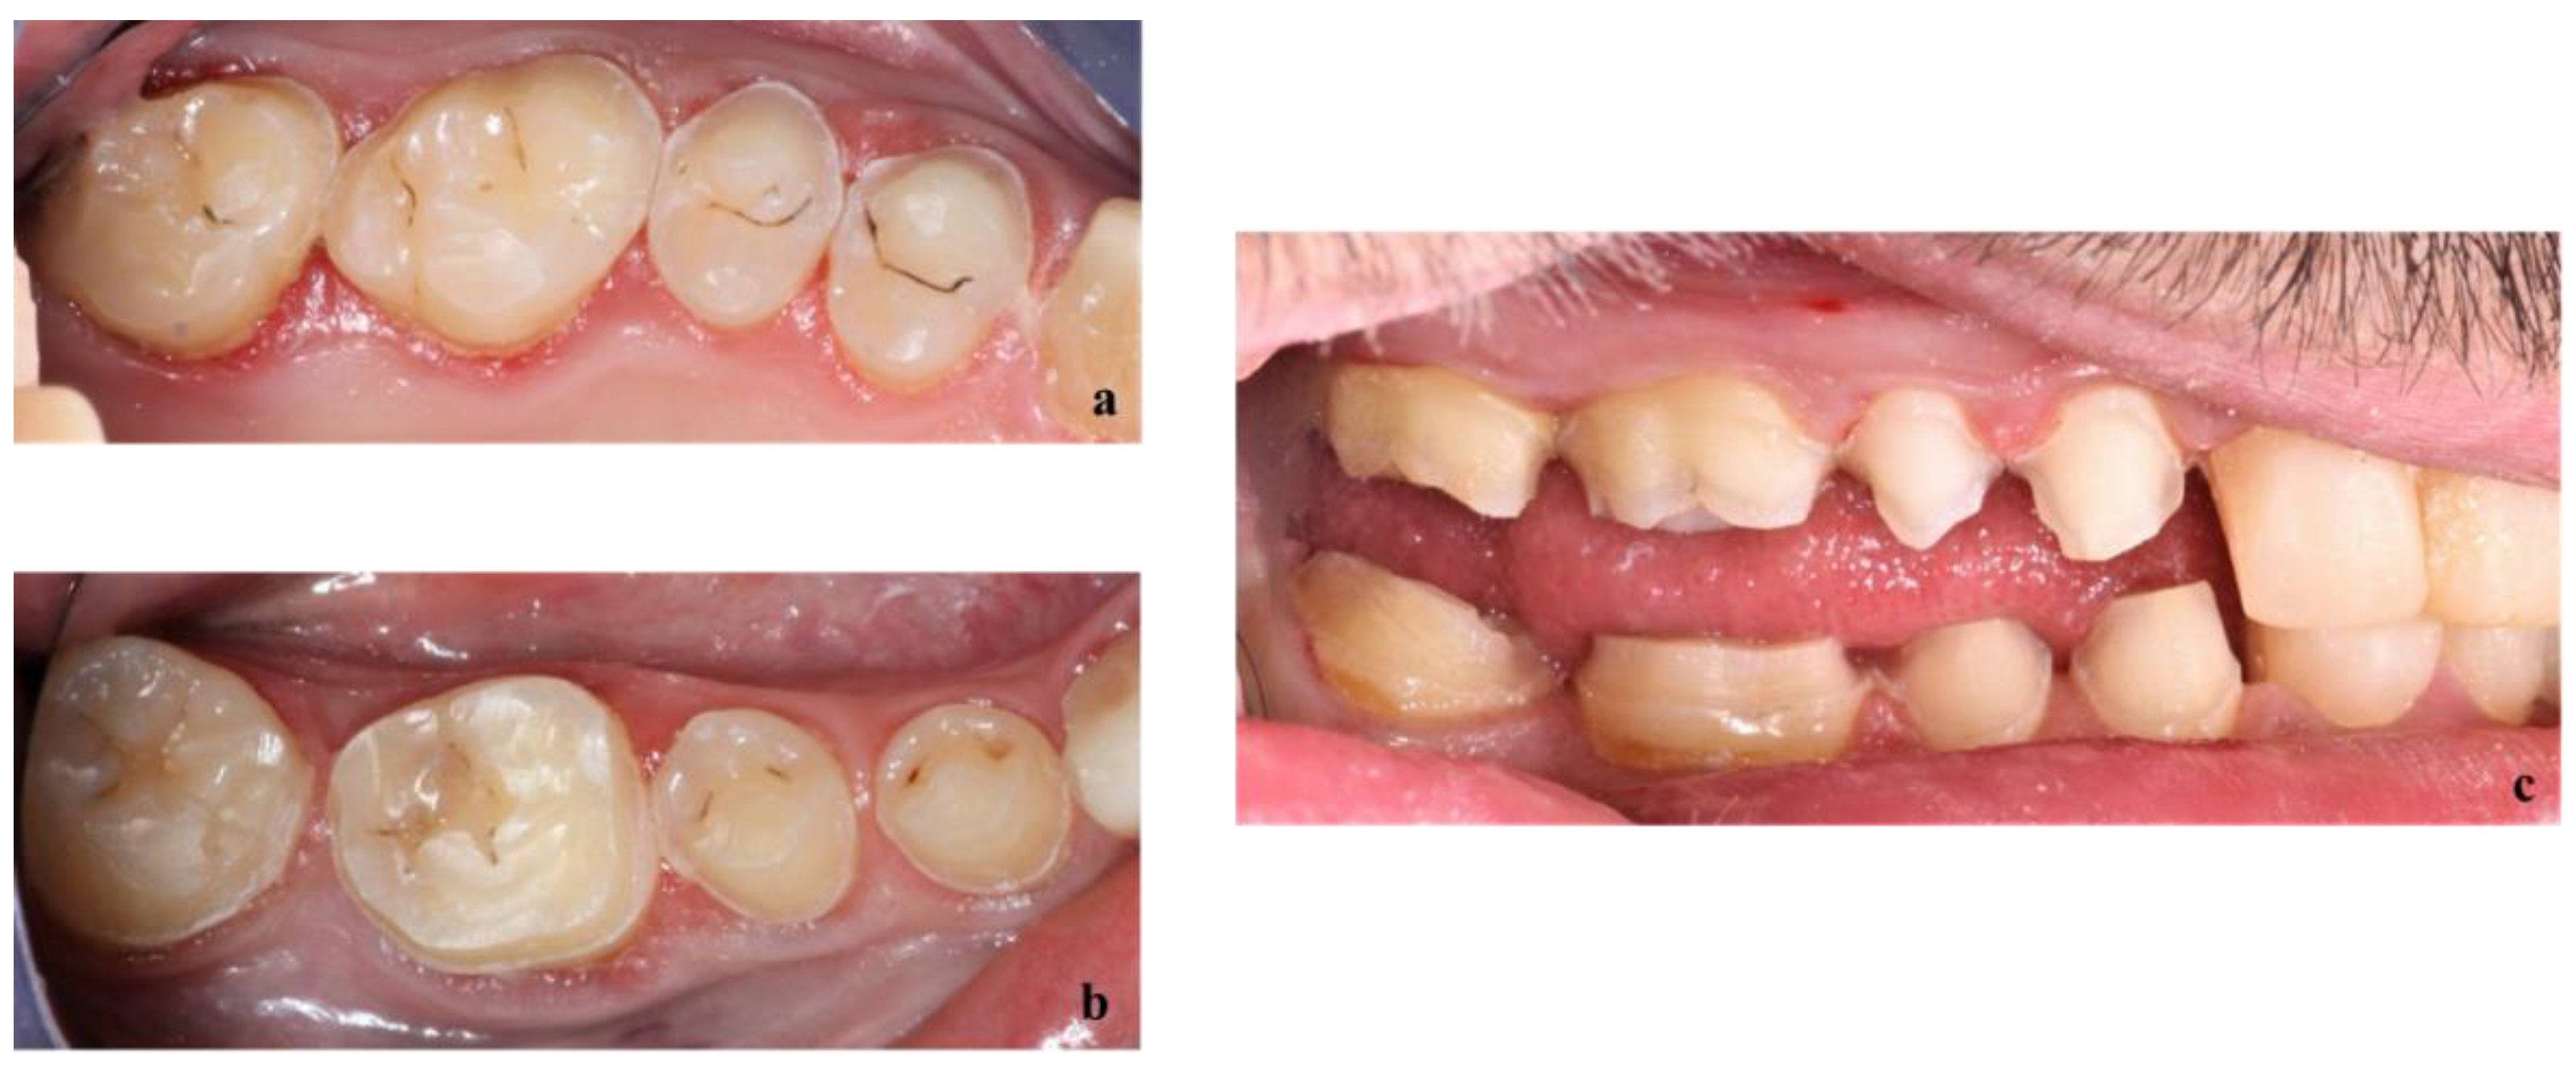

Teeth of the upper (a) and lower (b) right pre-molar and molar sectors were prepared through the mock-up as shown in Figure 8.

Figure 8.

Teeth preparation through the mock-up of upper (a) and lower (b) right premolars and molars.

Once teeth were prepared, an optical impression of the preparations was made, and a temporary resin (Structur Premium, VOCO) was placed on the teeth with silicone keys (Figure 9) to protect them for a week, the time needed for the prosthetic laboratory to prepare the fixed prosthetic components.